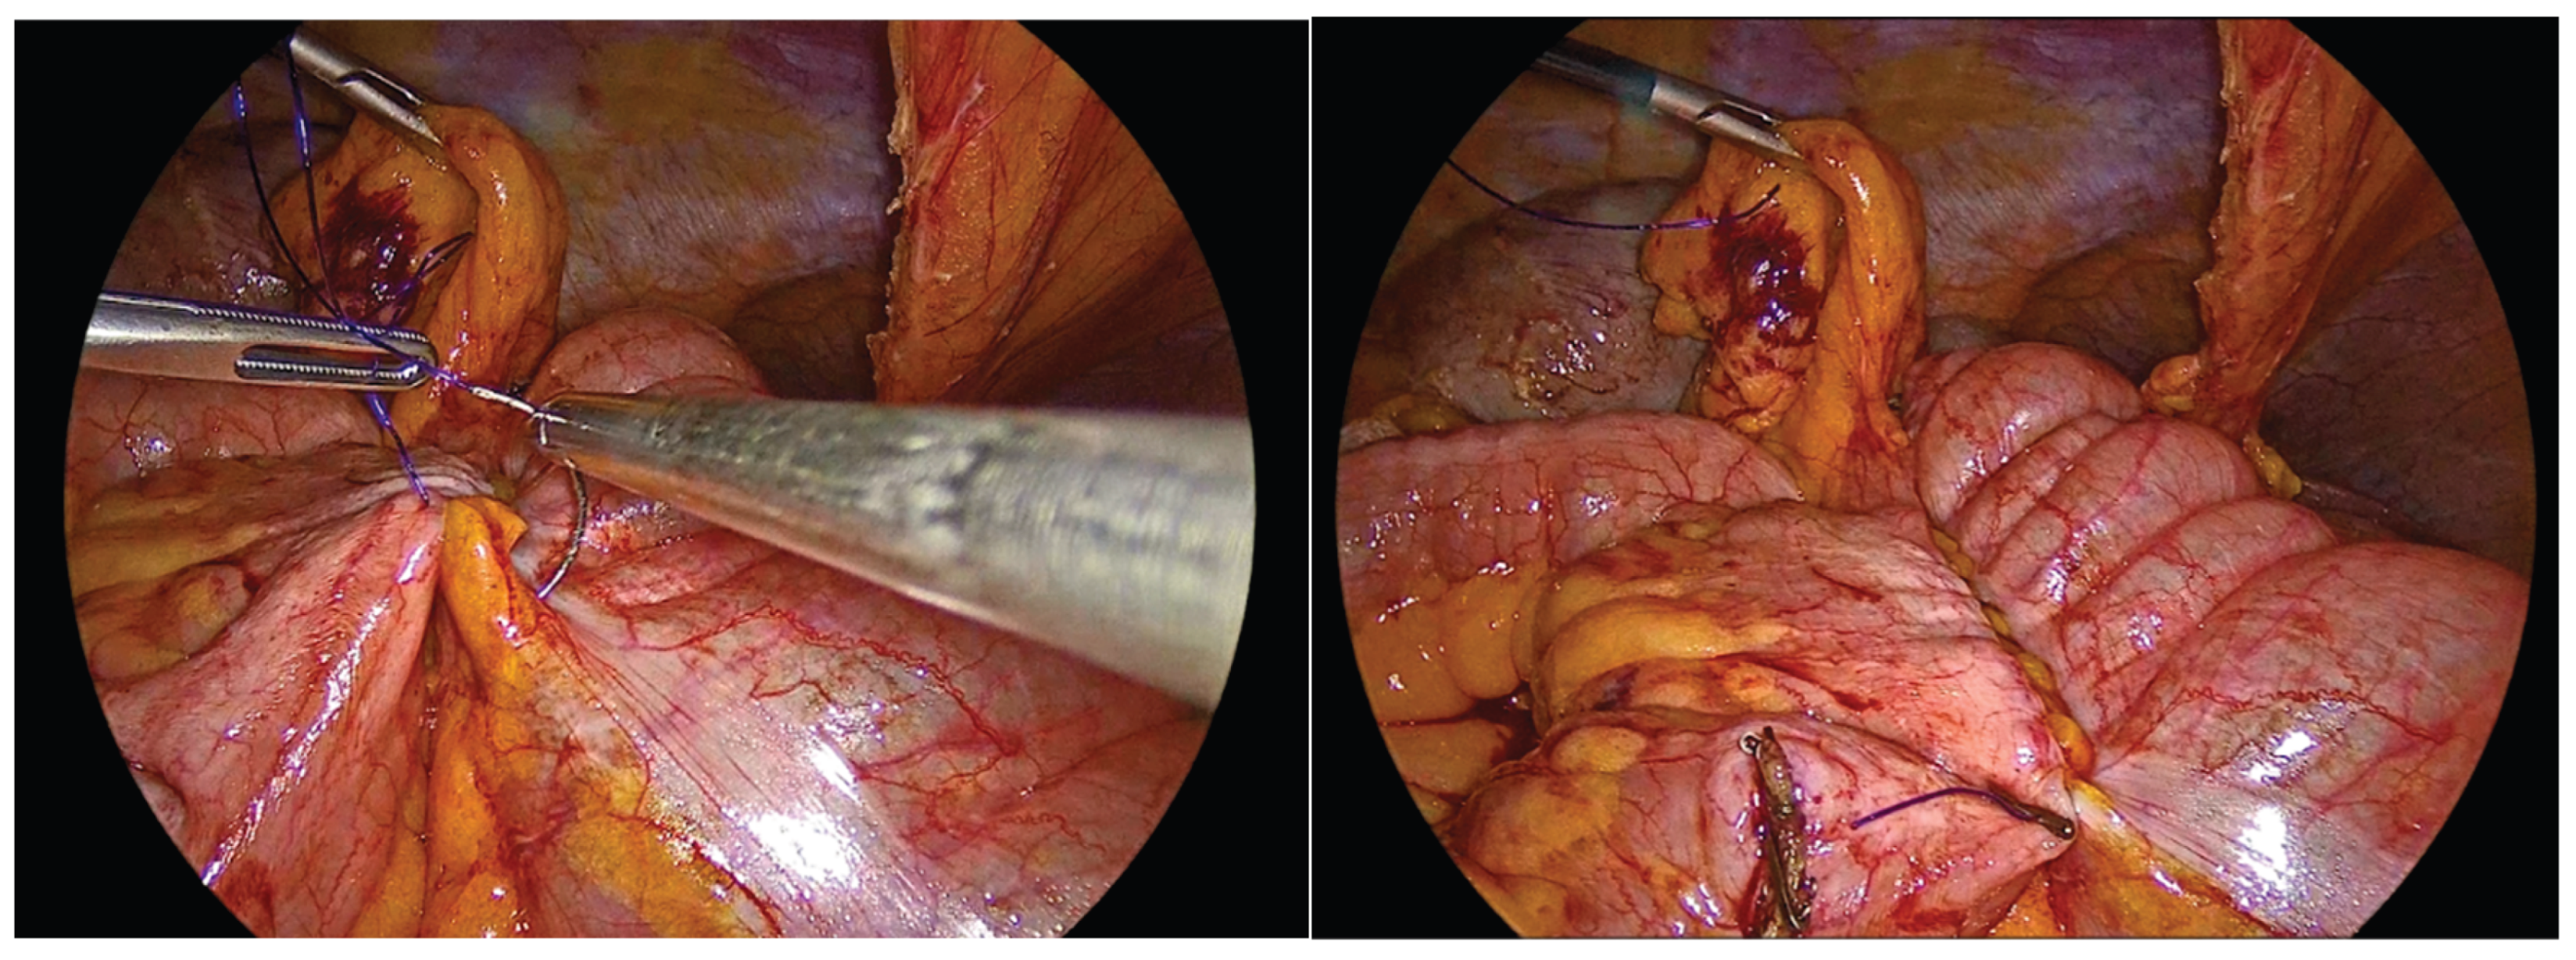

The transverse colon and terminal ileum are aligned in an isoperistaltic, side-to-side orientation, approximately 5 cm proximal to the stapled ends using barbed No.3-0 suture 15cm long. A single - layer handsewn intracorporeal anastomosis is then fashioned using a Vicryl No.3-0 suture 34cm long.

Figure 5. Alignment and positioning of the terminal ileum and transverse colon in an isoperistaltic, side-to-side configuration.

The anastomosis begins with a continuous seromuscular layer using a barbed 3-0 non - absorbable suture, extending for approximately 8 to 10 cm, providing reinforcement and support to the anastomosis.

Figure 6. Side to side isoperistaltic sutured alignment of transverse colon with ileum.

Enterotomies are subsequently created on the antimesenteric borders of both bowel segments, at approximately 1 cm from the outer suture line, with a length of 3 to 4 cm.

Figure 7. Enterotomies of bowel ends.

The inner layer of the anastomosis is constructed using a continuous full-thickness absorbable 3-0 Vicryl Plus suture, initiated proximally to the surgeon. Suturing proceeds from the proximal aspect toward the antimesenteric border, incorporating all the layers of the bowel lumen, with bites placed at intervals of 0,5 to 1 cm. Upon reaching the distal end of the enterotomy, the suture is continued along the opposite side, and the anterior layer of the anastomosis is completed after reaching back the proximal initial part of the anastomosis and tying the suture and to the initial knot.

Figure 8. First suture of the anastomosis, using an absorbable 3-0 Vicryl Plus suture.

Figure 9. The inner layer of the anastomosis.

Figure 10. Completion of the inner full-thickness layer of the anastomosis and transition to construction of the anterior layer.

Figure 11. Anterior outer layer of the anastomosis.

Figure 12. The completed single-layer handsewn intracorporeal anastomosis.

In order to facilitate the ease of the construction of this anastomosis, we use right-hand, left-hand, back-hand, and fore-hand techniques. We take care not to evert the mucosa of the colon or ileum, but on the contrary to invert both mucosa into the suture line. We also try to be precise with the sutures and as far as possible the anastomosis to be symmetric. Completion of the anastomosis is followed by meticulous inspection of the suture line and stapled bowel ends to ensure adequate hemostasis and the absence of hematoma formation.